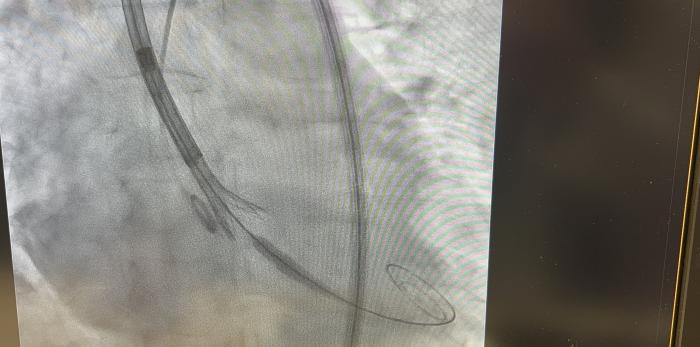

Su aplicación permite obtener imágenes del interior del cuerpo mediante pruebas como radiografías o escáneres, así como guiar procedimientos clínicos en tiempo real mediante el uso de rayos X, lo que facilita a los profesionales visualizar el interior del organismo mientras actúan, por ejemplo, en intervenciones cardiacas o en el tratamiento de cálculos renales, o tratar enfermedades mediante el uso controlado de radiación.

Por su parte, la braquiterapia permite administrar la radiación directamente en la zona afectada mediante la introducción temporal de fuentes radiactivas, lo que facilita una alta precisión en el tratamiento. En Aragón, se aplica a unos 90 pacientes al año, en tumores prostáticos y ginecológicos.